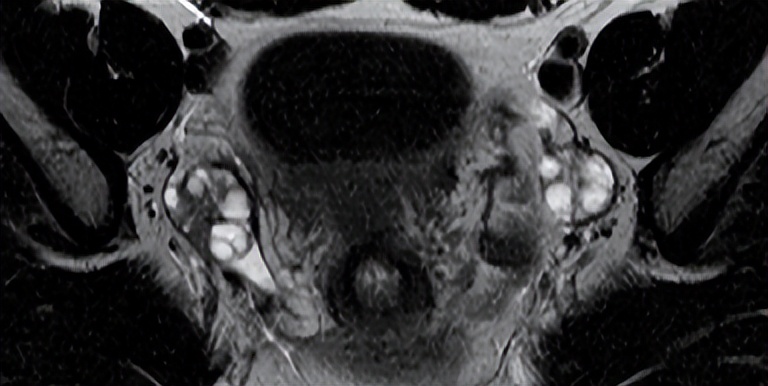

功能性滤泡性卵巢囊肿是常见的良性病变,通常表现为单房、薄壁病变,伴有水样信号(图76.1,轴位T2WI)。无功能性囊性病变是鉴别诊断因素,但由于肿瘤形成可能看起来相似,因此应在6周内通过超声重新评估新诊断的30 mm以上卵泡囊肿。滤泡囊肿的囊壁增强不如黄体囊肿。后者的壁通常也较厚,如图76.2A的冠状T2WI(白色箭头)所示,(B) CE T1WI显示管壁明显增强。

▲ 图76.1